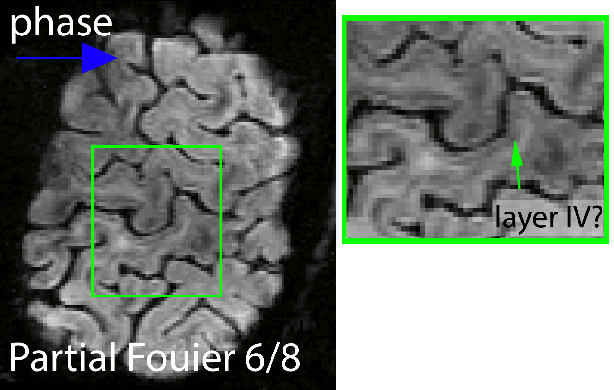

Example 2 of the blurring with and without partial Fourier imaging

I found that that when I was aiming for high-resolutions, it is beneficial to refrain from the application of partial Fourier (PF) imaging as much as possible. For the long readout durations at high-resolutions and the fast T2/T2*-decay at high field strengths results in even stronger blurring of partial-Fourier.